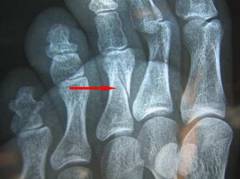

Рентгенография ступни в одной или двух проекциях позволяет с высокой точностью выявить перелом. Она помогает определить локализацию и положение отломков, что важно для выбора лечения.

В диагностике перелома пальца ноги важна рентгенография стопы в одной или двух проекциях. Это исследование позволяет с высокой точностью (95-99%) выявить перелом. Рентген в двух проекциях помогает точно определить местоположение перелома и положение костных отломков, что позволяет оценить сложность травмы и выбрать оптимальную тактику лечения.